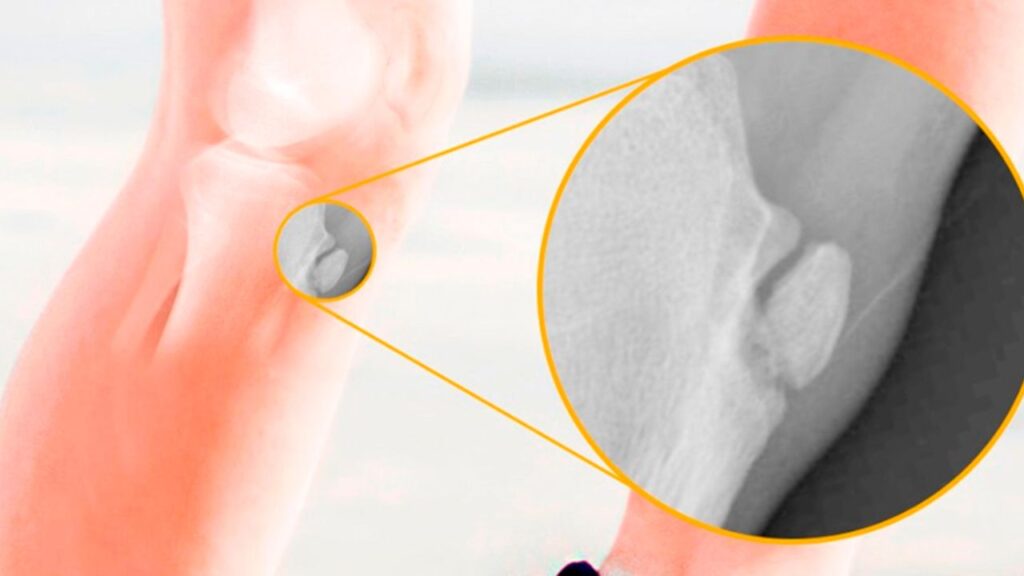

Para entender Osgood-Schlatter, precisamos focar na região do joelho. Na parte da frente da perna, logo abaixo da patela (rótula), há uma proeminência óssea chamada tuberosidade da tíbia. É nesse ponto que se insere o tendão patelar, que conecta a patela ao osso da canela (tíbia). Durante o estirão de crescimento, essa região é mais vulnerável e as placas de crescimento ainda não estão totalmente fechadas, tornando-a sensível a tensões.

A patologia de Osgood-Schlatter é uma osteocondrose por tração. Isso significa que é uma inflamação e irritação crônica na região da tuberosidade da tíbia, causada pela tensão repetitiva e excessiva exercida pelo tendão patelar. Em outras palavras, quando a criança ou adolescente pratica atividades que envolvem corrida, saltos e chutes, o quadríceps (músculo da coxa) puxa o tendão patelar, que por sua vez exerce tração na tuberosidade da tíbia imatura, gerando microtraumas e inflamação.

O diagnóstico é essencialmente clínico e realizado por um ortopedista pediátrico ou especialista em joelho. O médico irá avaliar a história da criança (idade, nível de atividade física) e realizar um exame físico que reproduza a dor e identifique a proeminência e sensibilidade na tuberosidade da tíbia. Geralmente, exames de imagem como o raio-X não são estritamente necessários para o diagnóstico, mas podem ser usados para descartar outras condições ou para acompanhar a evolução da proeminência óssea.